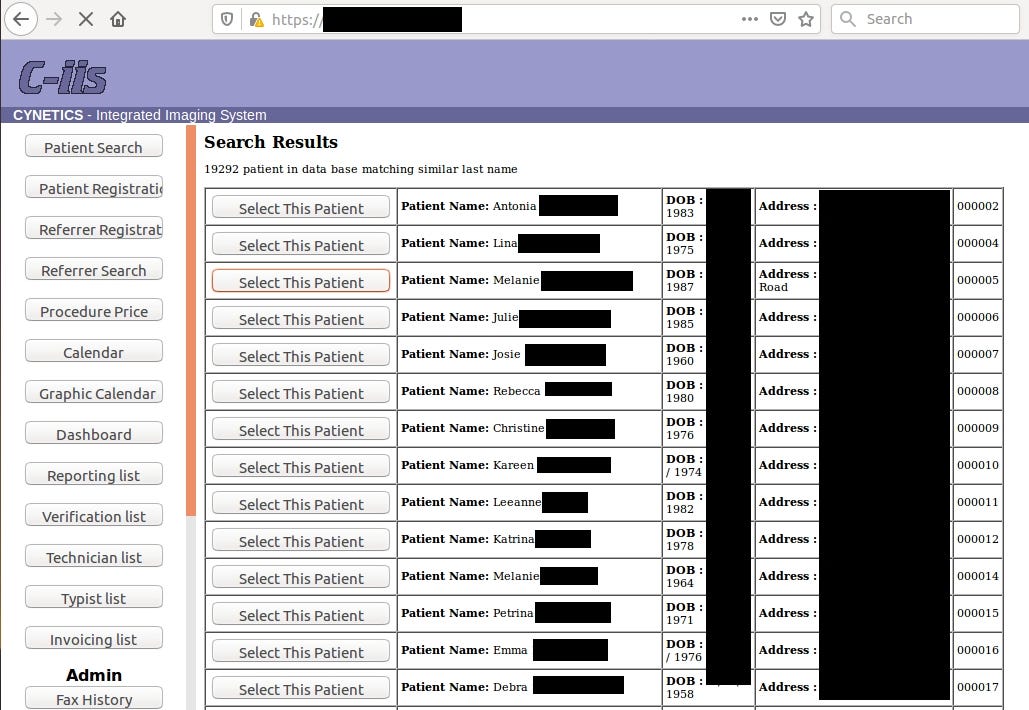

In this case leak contained 4,5 TB of data including radiology photos of pregnancies with diagnosis (almost 2M images!), invoices or personal patient’s data.

Going back to the main topic and the most important data in the leak, each patient has from 10 up to 40 radiology photos with description.

Frankly speaking, it says nothing for me but for someone acquainted with the topic it’s trove of information about health of patient and her fetus.

If someone is reading this article and used their service, she should be aware that her medical and personal data might have been compromised.